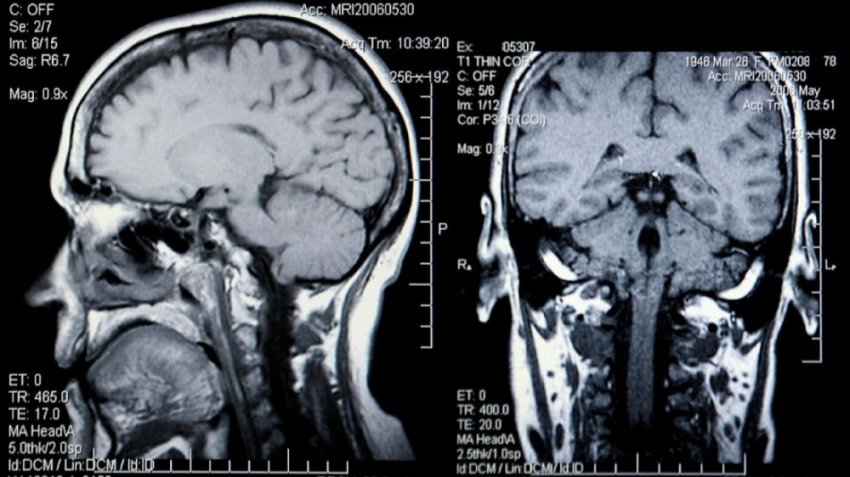

Магнитно-резонансная томография (МРТ) — это исследование, которое позволяет вашему врачу увидеть подробные изображения ваших органов и тканей. В МРТ-аппарате используется большой магнит, радиоволны и компьютер, чтобы делать детальные снимки поперечных сечений внутренних органов и тканей.

Сканер выглядит как трубка со столом, на котором вы попадаете в туннель машины для сбора данных. В отличие от компьютерных томографов или рентгеновских лучей, в которых используется ионизирующее излучение, которое, как известно, повреждает ДНК, МРТ использует магнитные поля.

Изображения из МРТ дают врачам лучшую информацию о патологиях, опухолях, кистах и специфических проблемах с сердцем, печенью, маткой, почками и другими органами.